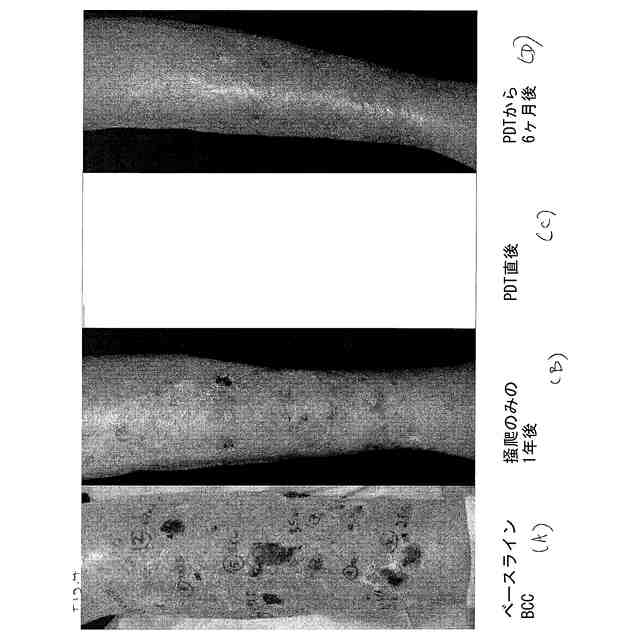

【0002】

本発明は、一般的には、加熱と共に赤色光光線力学的療法を用いて、皮膚の疾患及び障

害を処置する方法に関する。特定の実施形態において、本発明は、熱処理された皮膚に対

して、赤色光光線力学的療法を用いて、座瘡、非黒色腫皮膚がん(NMSC)、光線性角

化症(AK)又は播種性表在性光線性汗孔角化症(DSAP)を処置する方法に関する。